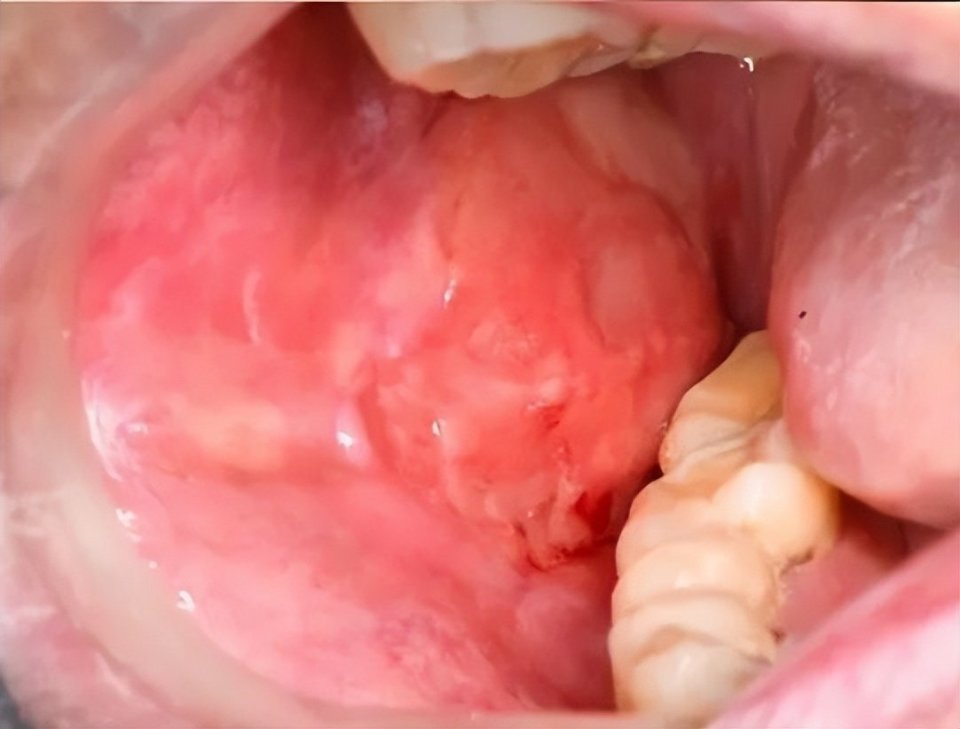

诊断性口腔表征:移植后口腔黏膜出现苔藓样改变,表现为角化过度的白色条纹或网状病变,可伴或不伴红斑、溃疡。一旦出现此典型表现,即高度提示口腔cGVHD。

溃疡形成及苔藓样损害(图片源自陶人川教授团队)

溃疡多继发于或合并苔藓样损害背景,常伴上述典型口腔表征。值得警惕的是,口腔cGVHD属于口腔潜在恶性疾患,对于长期不愈、质地改变的溃疡病损建议及时活检明确病损性质。